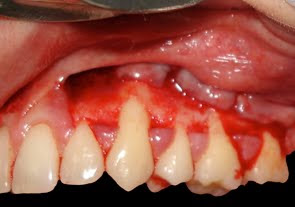

aspecto inicial da lesão a ser corrigida

notar estreita faixa de gengiva inserida

Incisão horizontal nas bases papilares